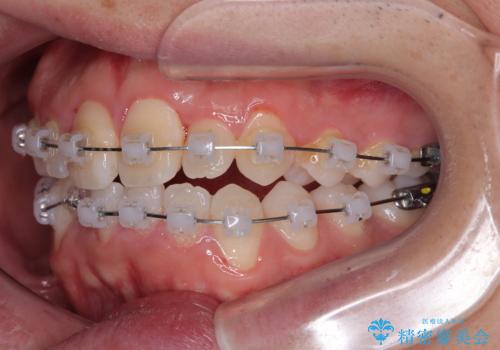

- 矯正装置

- クリアブラケット

- 1年2ヶ月

そのため今回は、プラスチックブラケット+メタルワイヤーによるクリアブラケットによる治療を選択しました。